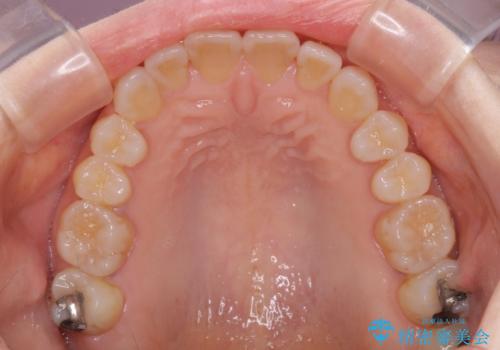

前歯の叢生と切端咬合 インビザラインによる矯正治療

上下前歯の先端同士が接触する切端咬合であったため、上顎は歯列を拡大し、下顎はIPR(歯と歯の間を削る)により叢生を解消しながら歯列を小さくすることとしました。

治療前から歯肉退縮が認められ、矯正治療により悪化する可能性が考えられたため、無理のない歯の移動と頻繁な経過観察を行いました。

切端咬合はスムーズに解消され、前歯の負担を軽減させることができました。